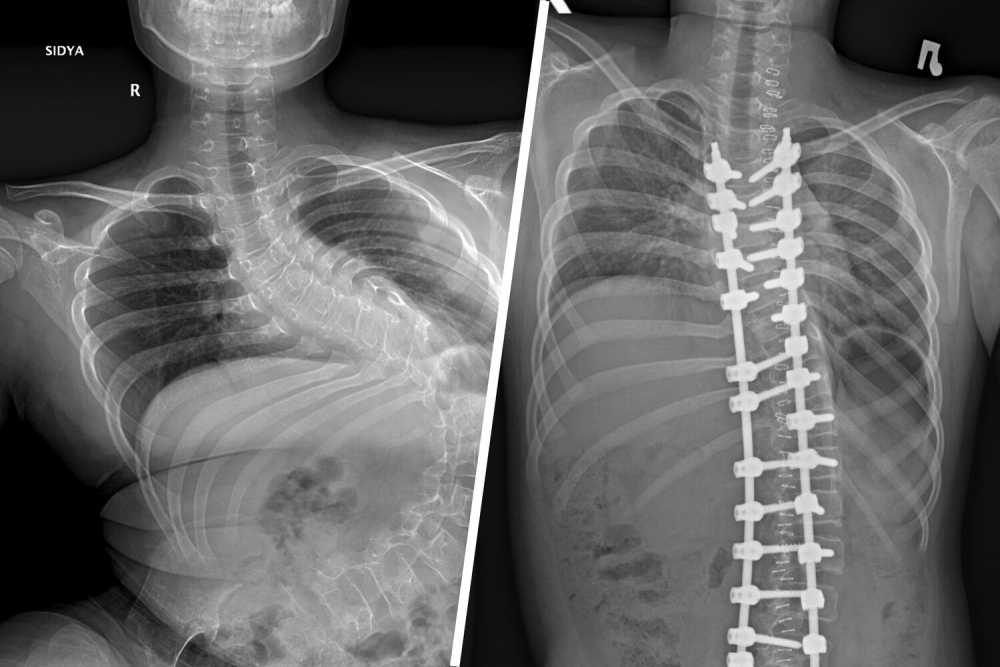

Сегодня несколько раз по новостям рассказывали про уникальную операцию мальчику с искривлением позвоночника 80° (!!!)

Если порыться в сети, можно найти рентгеновские снимки до/после. На всякий случай выложу под спойлер.

Скрытый текст

33211-pic4_zoom-1500x1500-27417.jpg.4f44153b09ca9db5ea058daf31fc55bd.jpg

А вообще, восхищаюсь врачами. Такая степень сколиоза - это уже угроза жизни постоянная, так как начинаются проблемы с дыханием.